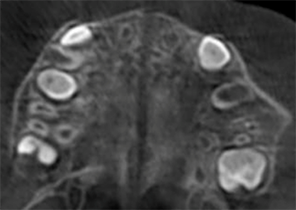

Antes de la disyunción con el sistema Invisalign Palatal Expander

Después de la disyunción con el sistema Invisalign Palatal Expander

Después del tratamiento Invisalign First

Informe de caso 1

10 años, 0 meses de edad, 18 etapas con dispositivos Invisalign Palatal Expander

Cortesía de la Dra. Sandra Khong Tai